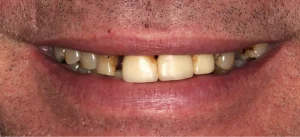

This gentleman felt that he had let his mouth go and was ready to get them sorted out. Even though he had most of his teeth, they were heavily decayed, abscessed, split and loose. Regrettably, his upper and lower teeth were past saving and were removed.

We placed eight upper jaw and six lower jaw implants. These were then joined with a bar.

Below left, you can see the inside of his denture with the metal sleeve that fits onto the bar. The custom-made bar is pictured on the right. Although the bars look different initially, patients love the bar’s stability for their dentures. The dentures are simple to remove and place. There’s no movement on eating, and cleaning and maintaining the implants long-term is easier.